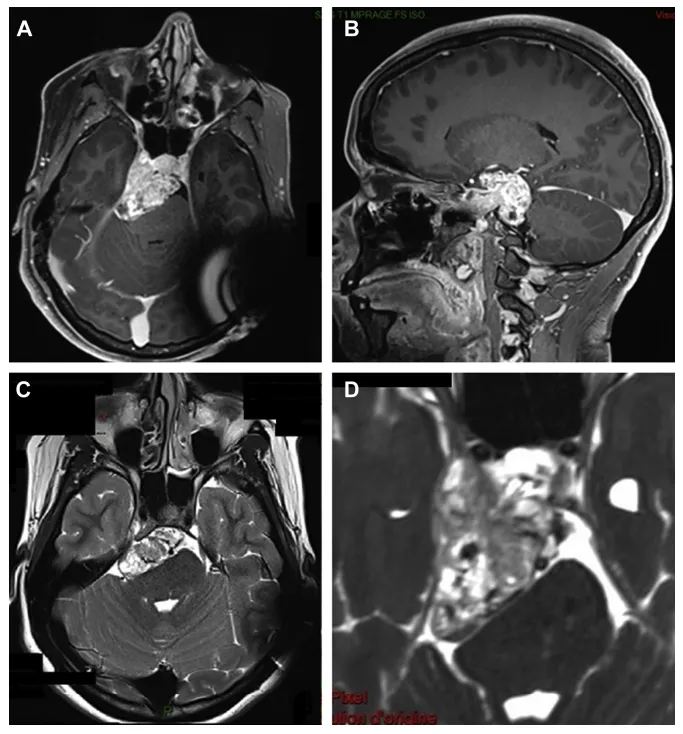

蹊跷的是,路易丝初诊时,CT检查并未发现颅内出血或脑挫裂伤,仿佛一切只是轻微外伤。然而,严重的症状并没有随着时间缓解,进一步的核磁共振(MRI)检查发现:一个巨大的肿瘤正盘踞在她颅底危险的“岩斜区”,甚至已将生命中枢——脑干已经被挤压移位(图1A-C),符合起源于右侧动眼神经的神经鞘瘤特征!

更加精细的FIESTA序列清晰显示,肿瘤沿动眼神经走行,经海绵窦上壁突入窦内(图1D)。